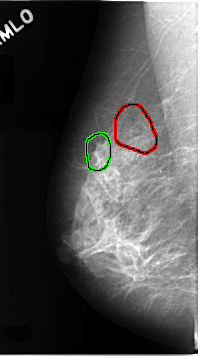

C_0068_1.LEFT_MLO

LEFT_MLO LINES 4688 PIXELS_PER_LINE 2496 BITS_PER_PIXEL 12 RESOLUTION 50 NON_OVERLAY

FILE: C_0068_1.RIGHT_MLO.OVERLAY

TOTAL_ABNORMALITIES 2

ABNORMALITY 1

LESION_TYPE CALCIFICATION TYPE AMORPHOUS DISTRIBUTION SEGMENTAL

ASSESSMENT 5

SUBTLETY 3

PATHOLOGY MALIGNANT

TOTAL_OUTLINES 1

BOUNDARY

ABNORMALITY 2

LESION_TYPE MASS SHAPE ARCHITECTURAL_DISTORTION MARGINS SPICULATED